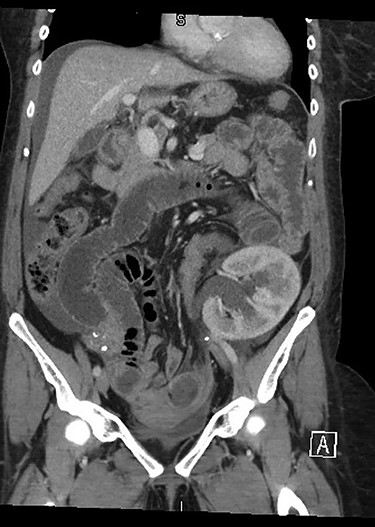

She presented to her local hospital due to sudden onset of severe abdominal pain with associated nausea, vomiting and diarrhoea. She was tachycardic though normotensive on presentation and found to have generalized severe abdominal pain. CT imaging revealed an SBO with an evidence of ischaemia as well as an obstructed ureter and renal collecting system within the allograft (Fig. 1). She underwent laparotomy, division of band adhesion in the left pelvis and 1.2 m of small bowel resected due to ischaemic necrosis with an end-to-end hand sewn anastomosis.

Initial CT demonstrating SBO and obstructed renal allograft/ureter (double obstruction).